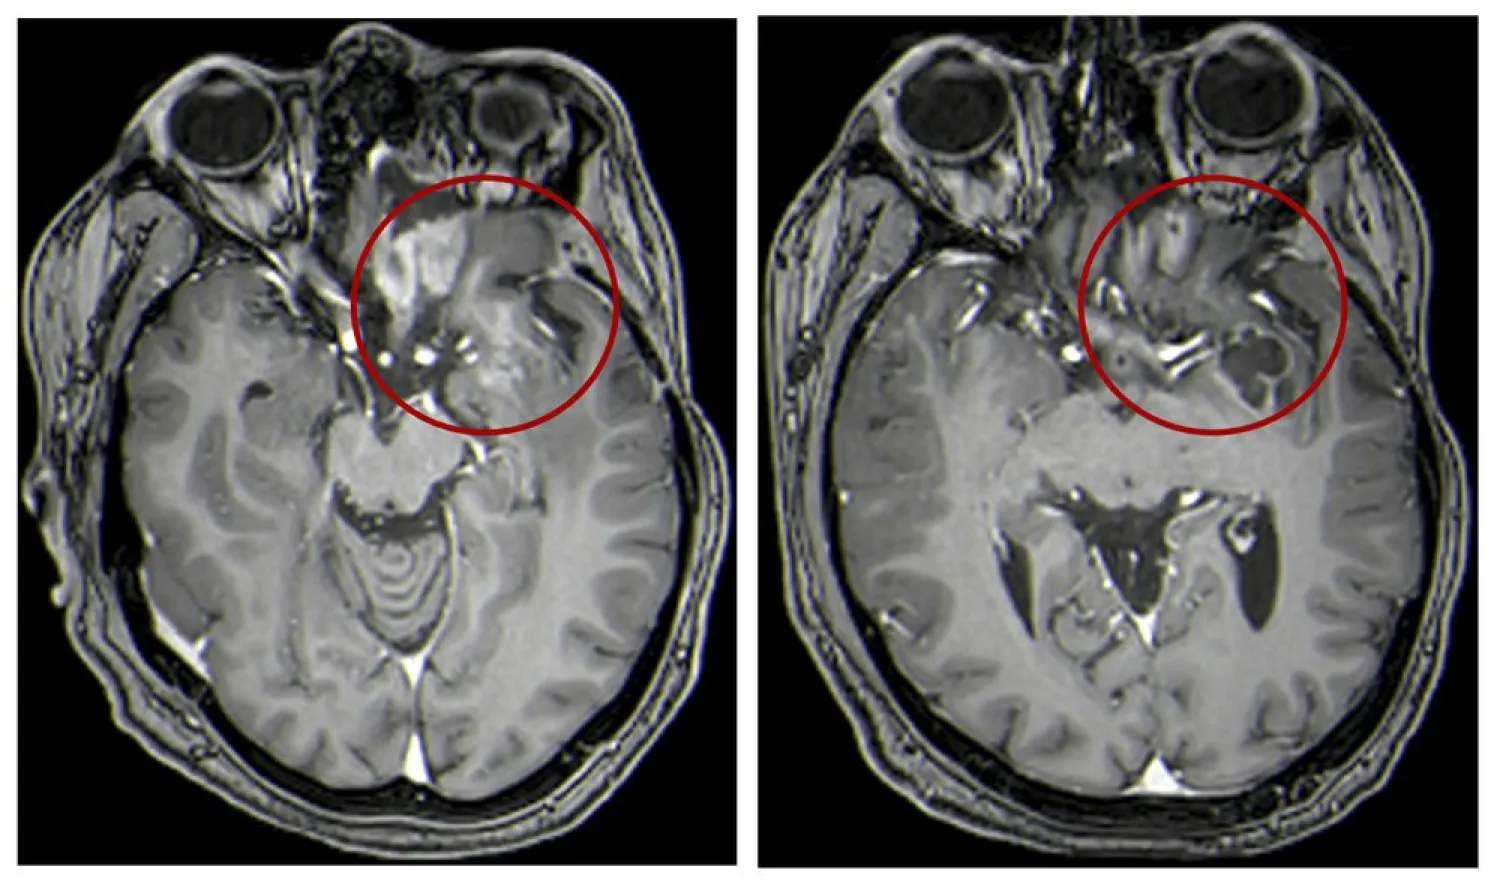

This combination of MRI images provided by the University of Alabama in April 2021 shows scans of a child with a brain tumor, before and after a treatment that involves using viruses to spur an immune system response to the cancerous cells. (UAB via AP)

For decades, a deadly type of childhood cancer has eluded science’s best tools. Now doctors have made progress with an unusual treatment: Dripping millions of copies of a virus directly into kids’ brains to infect their tumors and spur an immune system attack.

A dozen children treated this way lived more than twice as long as similar patients have in the past, doctors reported Saturday at an American Association for Cancer Research conference and in the New England Journal of Medicine.

Although most of them eventually died of their disease, a few are alive and well several years after treatment -- something virtually unheard of in this situation.

“Our goal is to improve on this,” possibly by trying it when patients are first diagnosed or by combining it with other therapies to boost the immune system, he said. The patients in the study were given the experimental approach after they failed other treatments.

The study involved gliomas, which account for 8% to 10% of childhood brain tumors. They’re usually treated with surgery, chemotherapy or radiation but they often recur. Once they do, survival averages just under six months.

In such cases, the immune system has lost the ability to recognize and attack the cancer, so scientists have been seeking ways to make the tumor a fresh target. They turned to the herpes virus, which causes cold sores and spurs a strong immune system response. A suburban Philadelphia company called Treovir developed a treatment by genetically modifying the virus so it would infect only cancer cells.

Through tiny tubes inserted in the tumors, doctors gave the altered virus to 12 patients ages 7 to 18 whose cancer had worsened after usual treatments. Half also received one dose of radiation, which is thought to help the virus spread.

Eleven showed evidence in imaging tests or tissue samples that the treatment was working. Median survival was just over a year, more than double what’s been seen in the past. As of last June -- the cutoff for analyzing these results -- four were still alive at least 18 months after treatment.